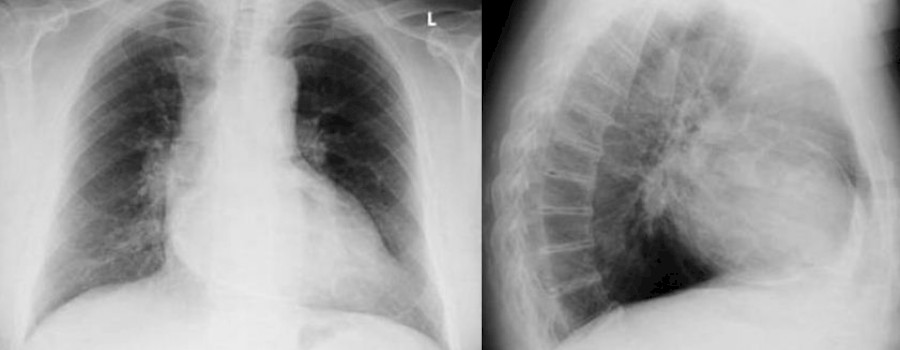

Unter einem Panzerherz versteht man eine Verdickung und Verkalkung des Herzbeutels, der eine Ausdehnung des Herzens im Rahmen seiner Füllungsphase nicht mehr uneingeschränkt zulässt.